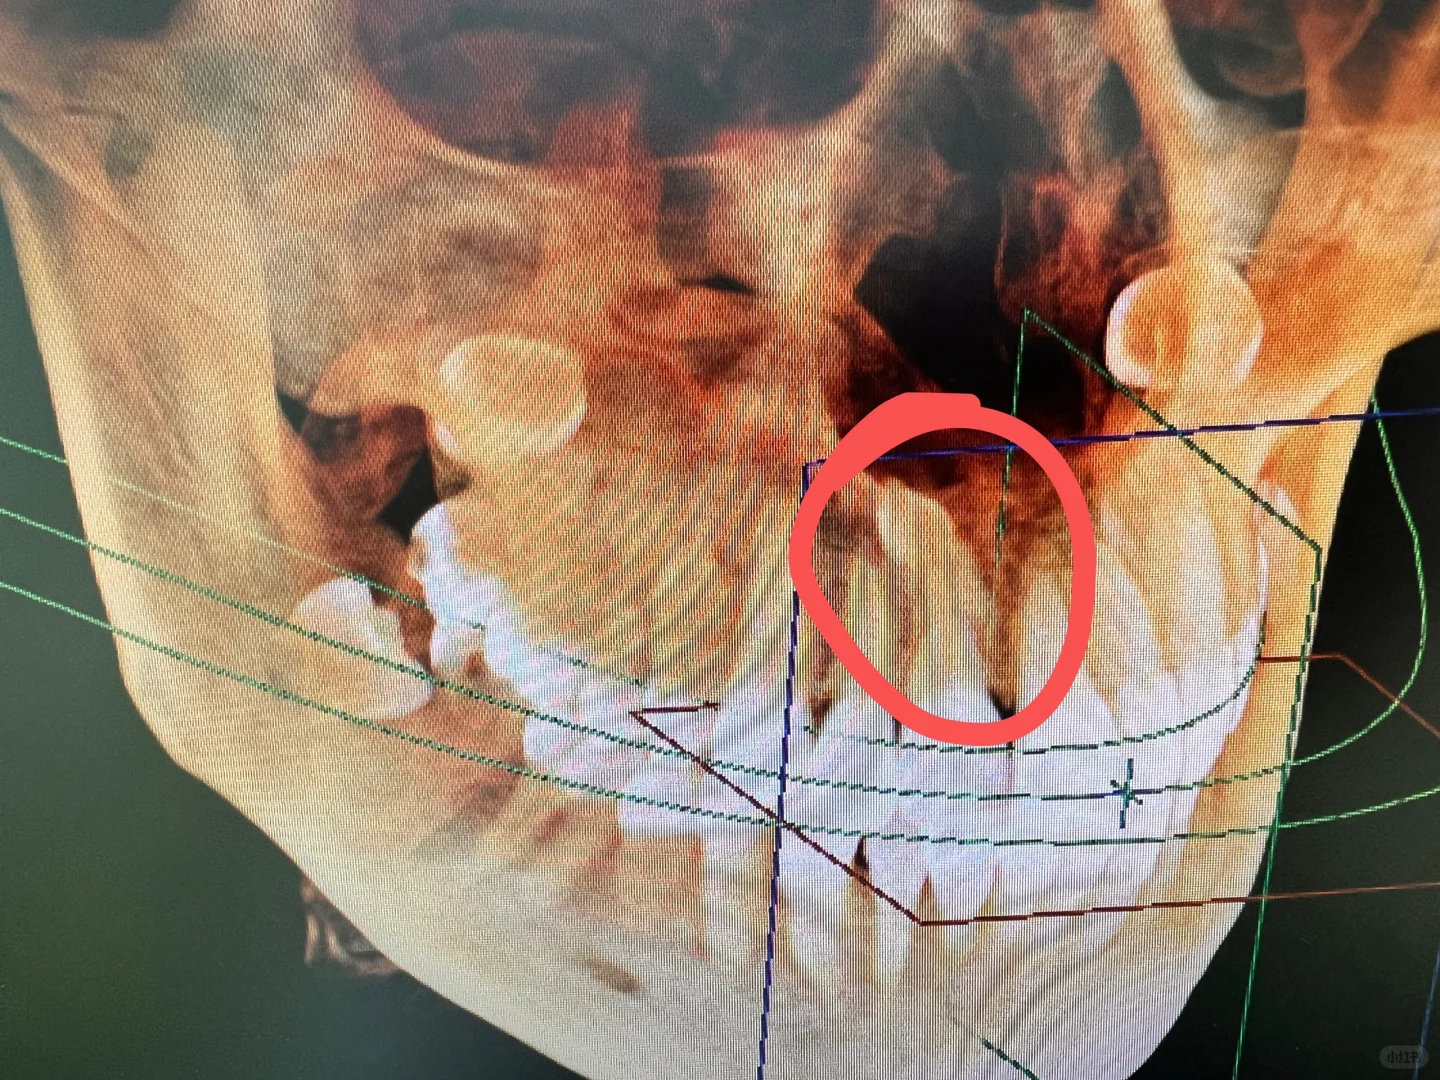

今天下午好不容易来一个拔牙的,还是外面**口腔转过来的,原来是在我们医院附近的**口腔做矫正,拍片发现有一颗埋伏多生牙,卡在两颗牙齿之间,影响矫正。

**口腔叫来我们医院口腔科拔掉,再回去矫正,恰好我接了,拍了cbct发现这颗牙倒着长的,牙尖在鼻腔底了,关键无论是唇侧还是腭侧,骨头都很厚,非常难拔!